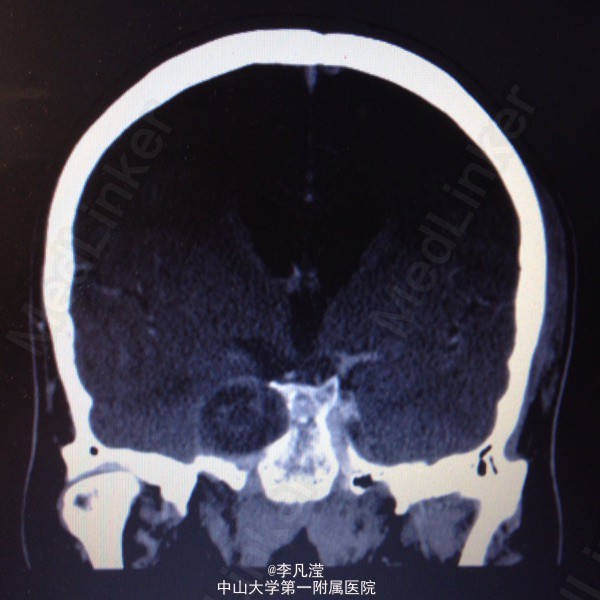

三叉神经鞘瘤一例

右侧中后颅窝底肿块,考虑三叉神经鞘瘤,右侧颞骨岩尖及海绵窦区骨质吸收,右侧麦氏孔扩大,侧脑室及第三脑室轻度积水。

右侧三叉神经鞘瘤